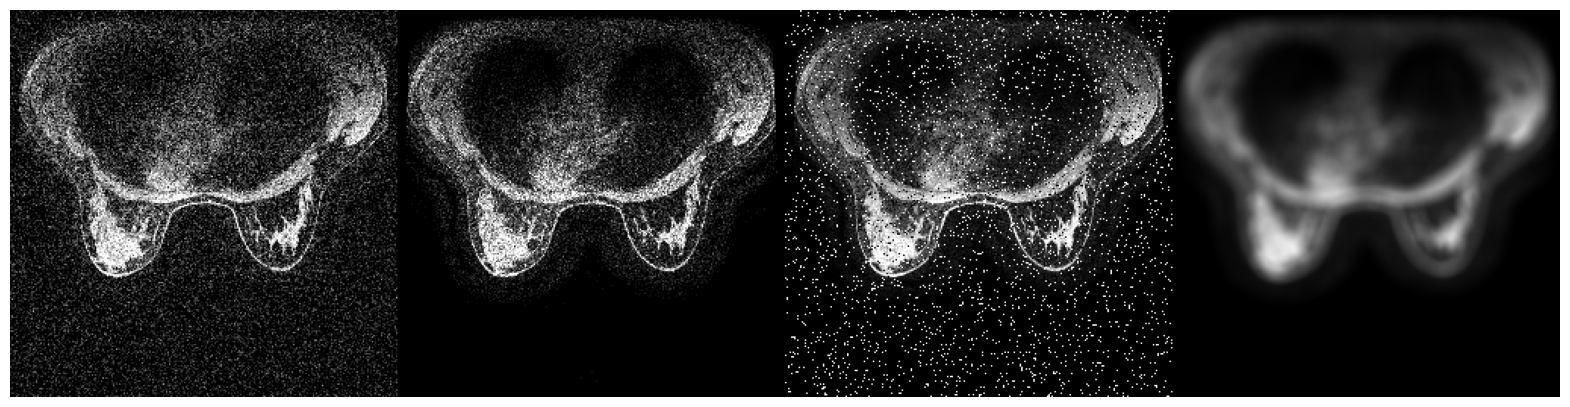

6.5.3 Validation with LUNG

The LUNG dataset is a collection of axial view lung CTs from three sources. The training and validation set consists of approximately 4000 slices extracted from 111 patient CT volumes from Pulmonary Fibrosis Progression (PFP), with their ground truth lung masks available in “CT Lung & Heart & Trachea segmentation” in Kaggle. We adopt another 90 axial view slices of lung CT volumes from “COVID-19 CT scans” showing lung with pneumonia as naturally occurring OOD data. (Access details in Section 4) The difference in the appearance of the COVID slices from the training set results not only from different imaging parameters but also from different infections. Each image is processed to have dimension 256×256256256256\times 256. We report below the mean IOUs and SBI of models trained on different models.

Training set IOUvalsubscriptIOU𝑣𝑎𝑙\mbox{IOU}_{val} IOUnoisysubscriptIOU𝑛𝑜𝑖𝑠𝑦\mbox{IOU}_{noisy} IOUOODsubscriptIOU𝑂𝑂𝐷\mbox{IOU}_{OOD} SBI

No Augmentation 0.982 0.938 0.962 2.650

Color Jitter 0.978 0.935 0.962 2.954

NST 0.978 0.941 0.962 3.014

Sep. Color Jitter 0.977 0.917 0.956 2.650

Negative Insertion 0.981 0.931 0.953 3.022

Random Resized Crop 0.942 0.793 0.853 2.534

Random Crop Reflect 0.979 0.672 0.943 2.128

Table 6: Performance of models trained on datasets with different augmentations when applied to the validation set, dataset with noise injected, and dataset with naturally occurred domain shifts for LUNG

.

Unlike in BFGT and FISH, as shown in Table 6, augmentations have much smaller effects on the performance of LUNG models. All augmentations that preserve targets’ shape yield models with very close performance on Validation, Noisy, and OOD data. Despite this, the effects of augmentations on SBI still align with our assumptions. Again, Random Resized Crop and Random Crop Reflect yield models with smaller SBI than the baseline, while the remaining augmentations increase each model’s SBI.

Refer to caption

(a) Image from "OSIC Pulmonary Fibrosis Progression" [38, 39]

(b) Image from "COVID-19 CT scans" [40, 41, 42]

(c) The image from "OSIC Pulmonary Fibrosis Progression" with (from left to right) Gaussian noise, shot noise, impulse noise, and defocus blur applied.

Figure 14: Samples from the three partitions of data domain in FISH

Augmentations, however, have negligible effects on this dataset. We explain this phenomenon by arguing that non-shape features may persist across multiple domains for LUNG. In LUNG, pixels associated with the lung have a texture style easily distinguishable from those associated with the rest of the image. The cooccurrence of high-intensity contours formed by cartilages also helps locate the lung. These features persist even across different image domains. In this case, the shape may not be the best discriminative feature in prediction capability. Non-shape features may be the more desirable feature sets to learn when optimizing the Cross-Entropy objective function. To avoid overstretching on interpreting the results, we will stop here with the conclusion that though Color Jitter and NST may suppress non-shape features, they barely hurt a model’s generalizability on Noisy and OOD data.